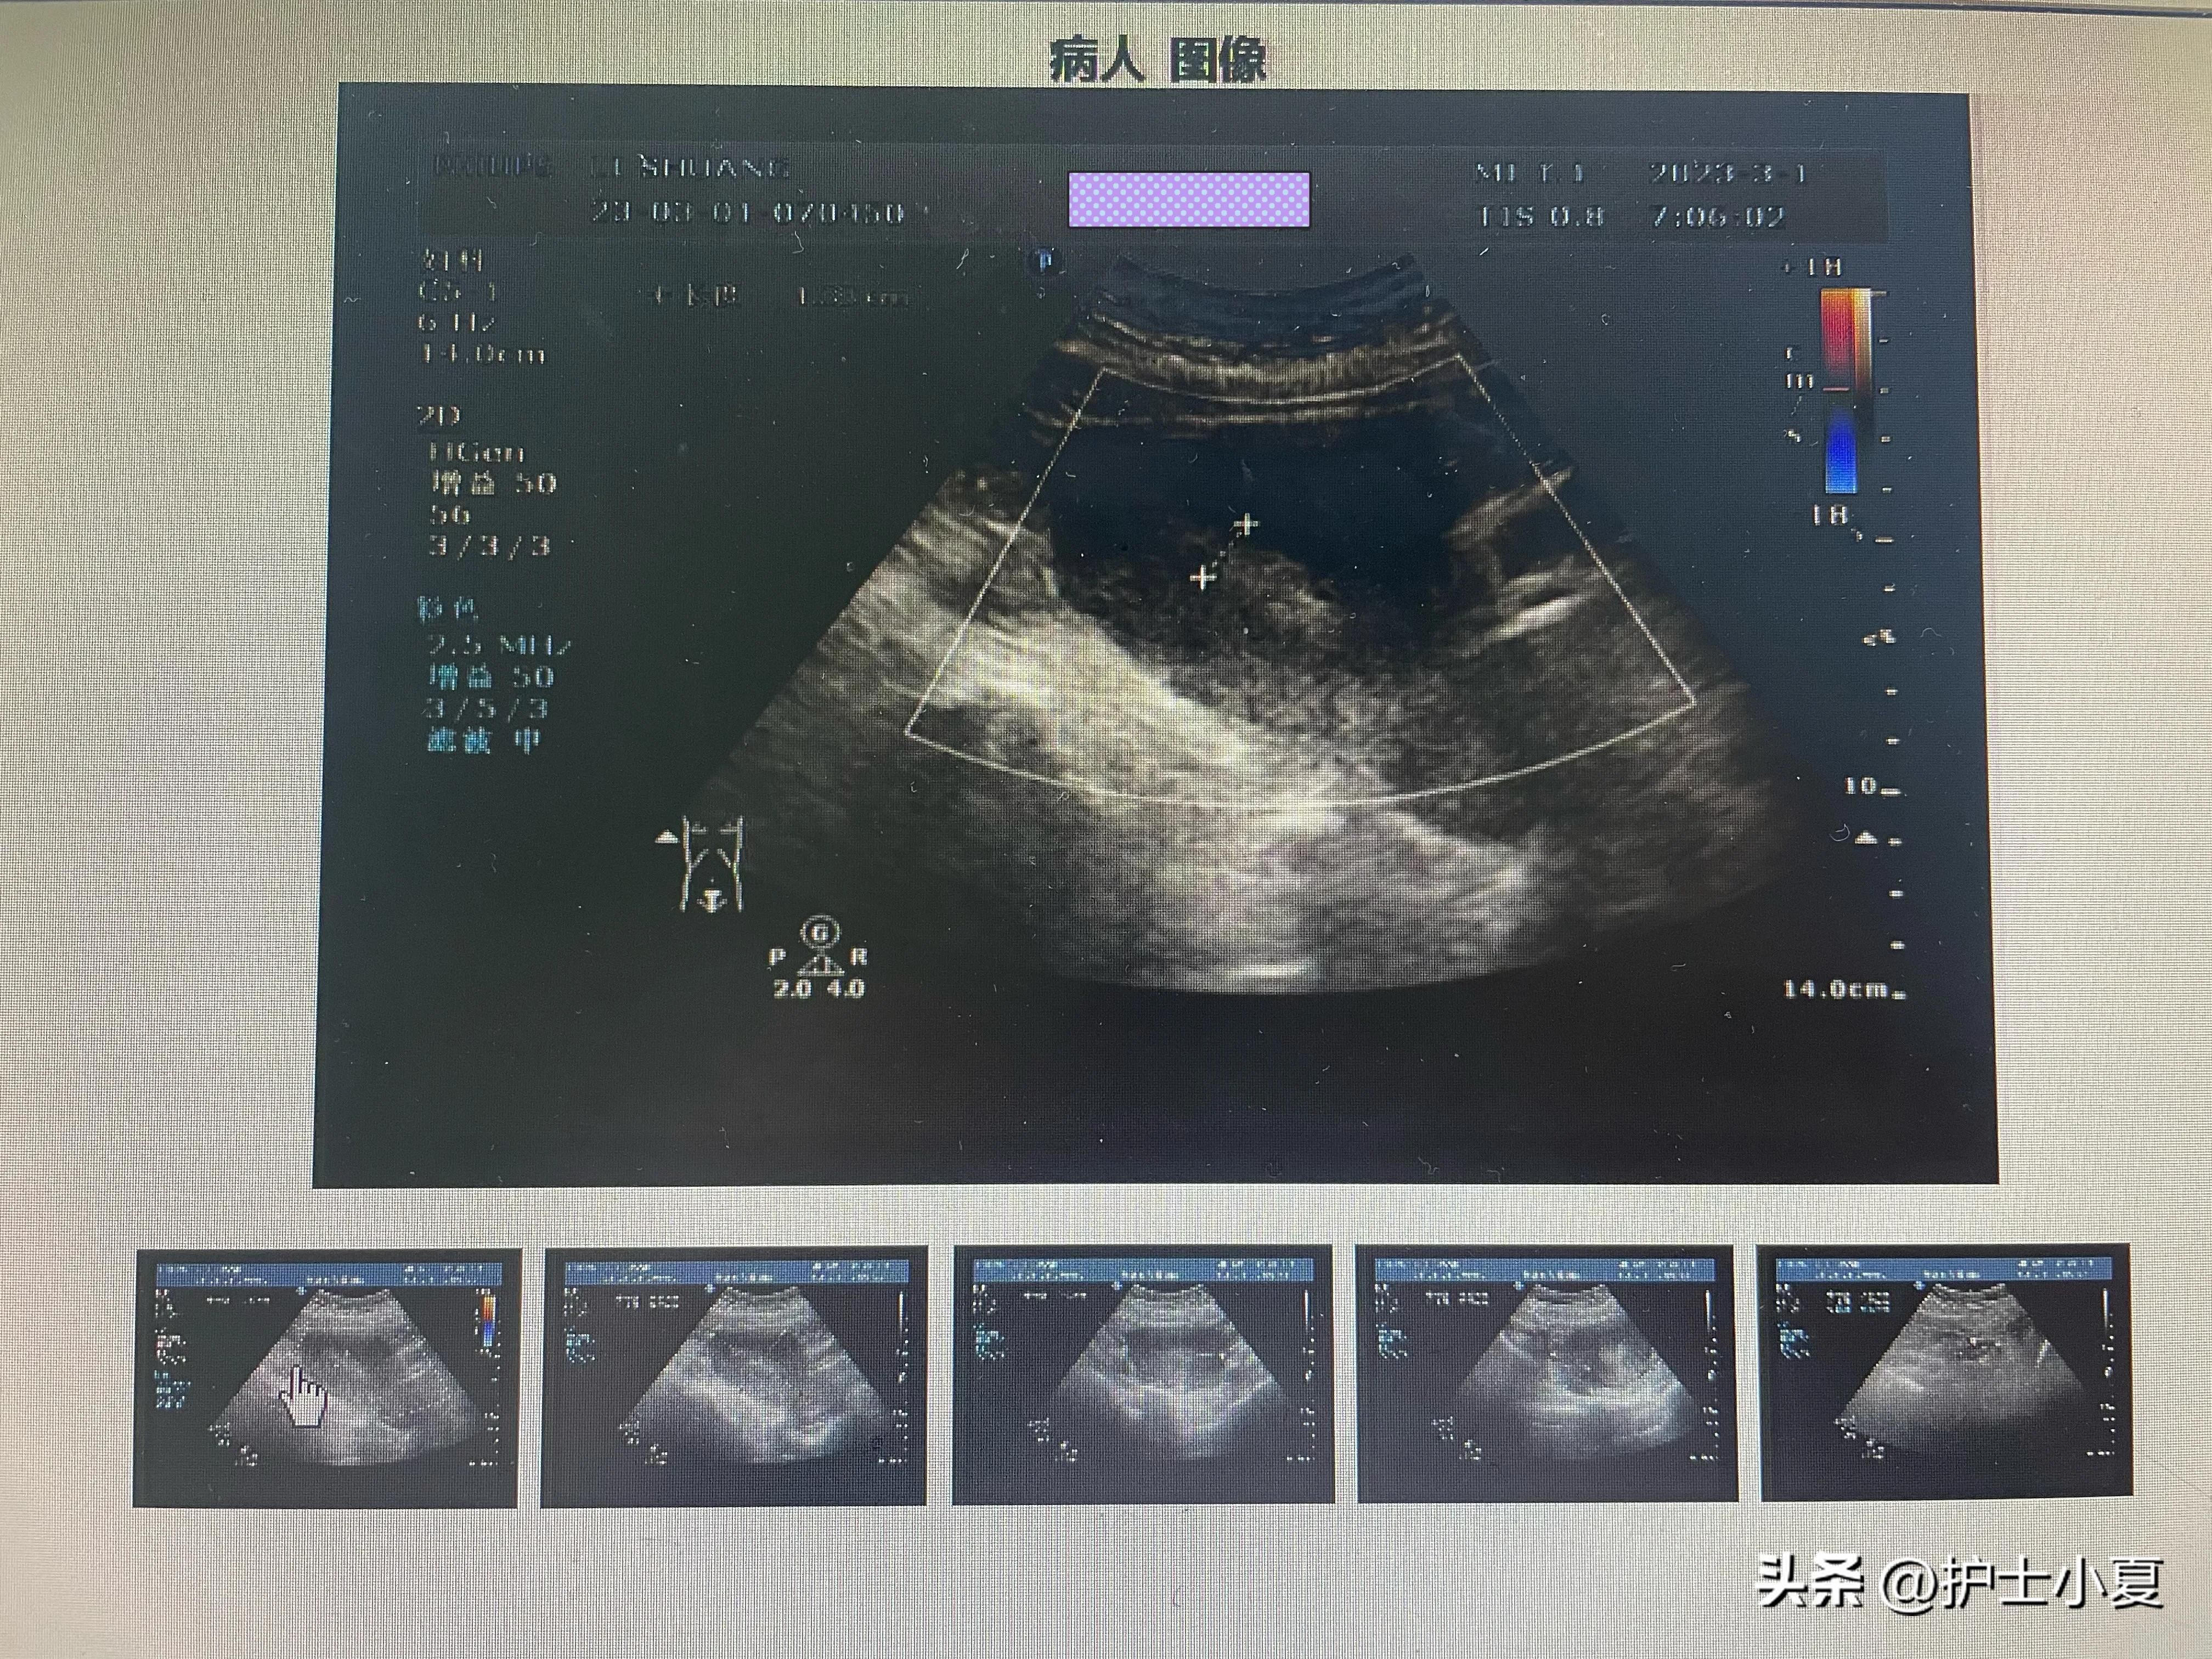

辅助检查: 超声 :双顶径:2Dmm,头臀长:68mm,NT:1.8mm,胎儿鼻骨可见,胎儿心率:152次/分,心律齐,羊水最大深度:33nm,胎盘附着于子宫后壁,胎盘厚:15mm。